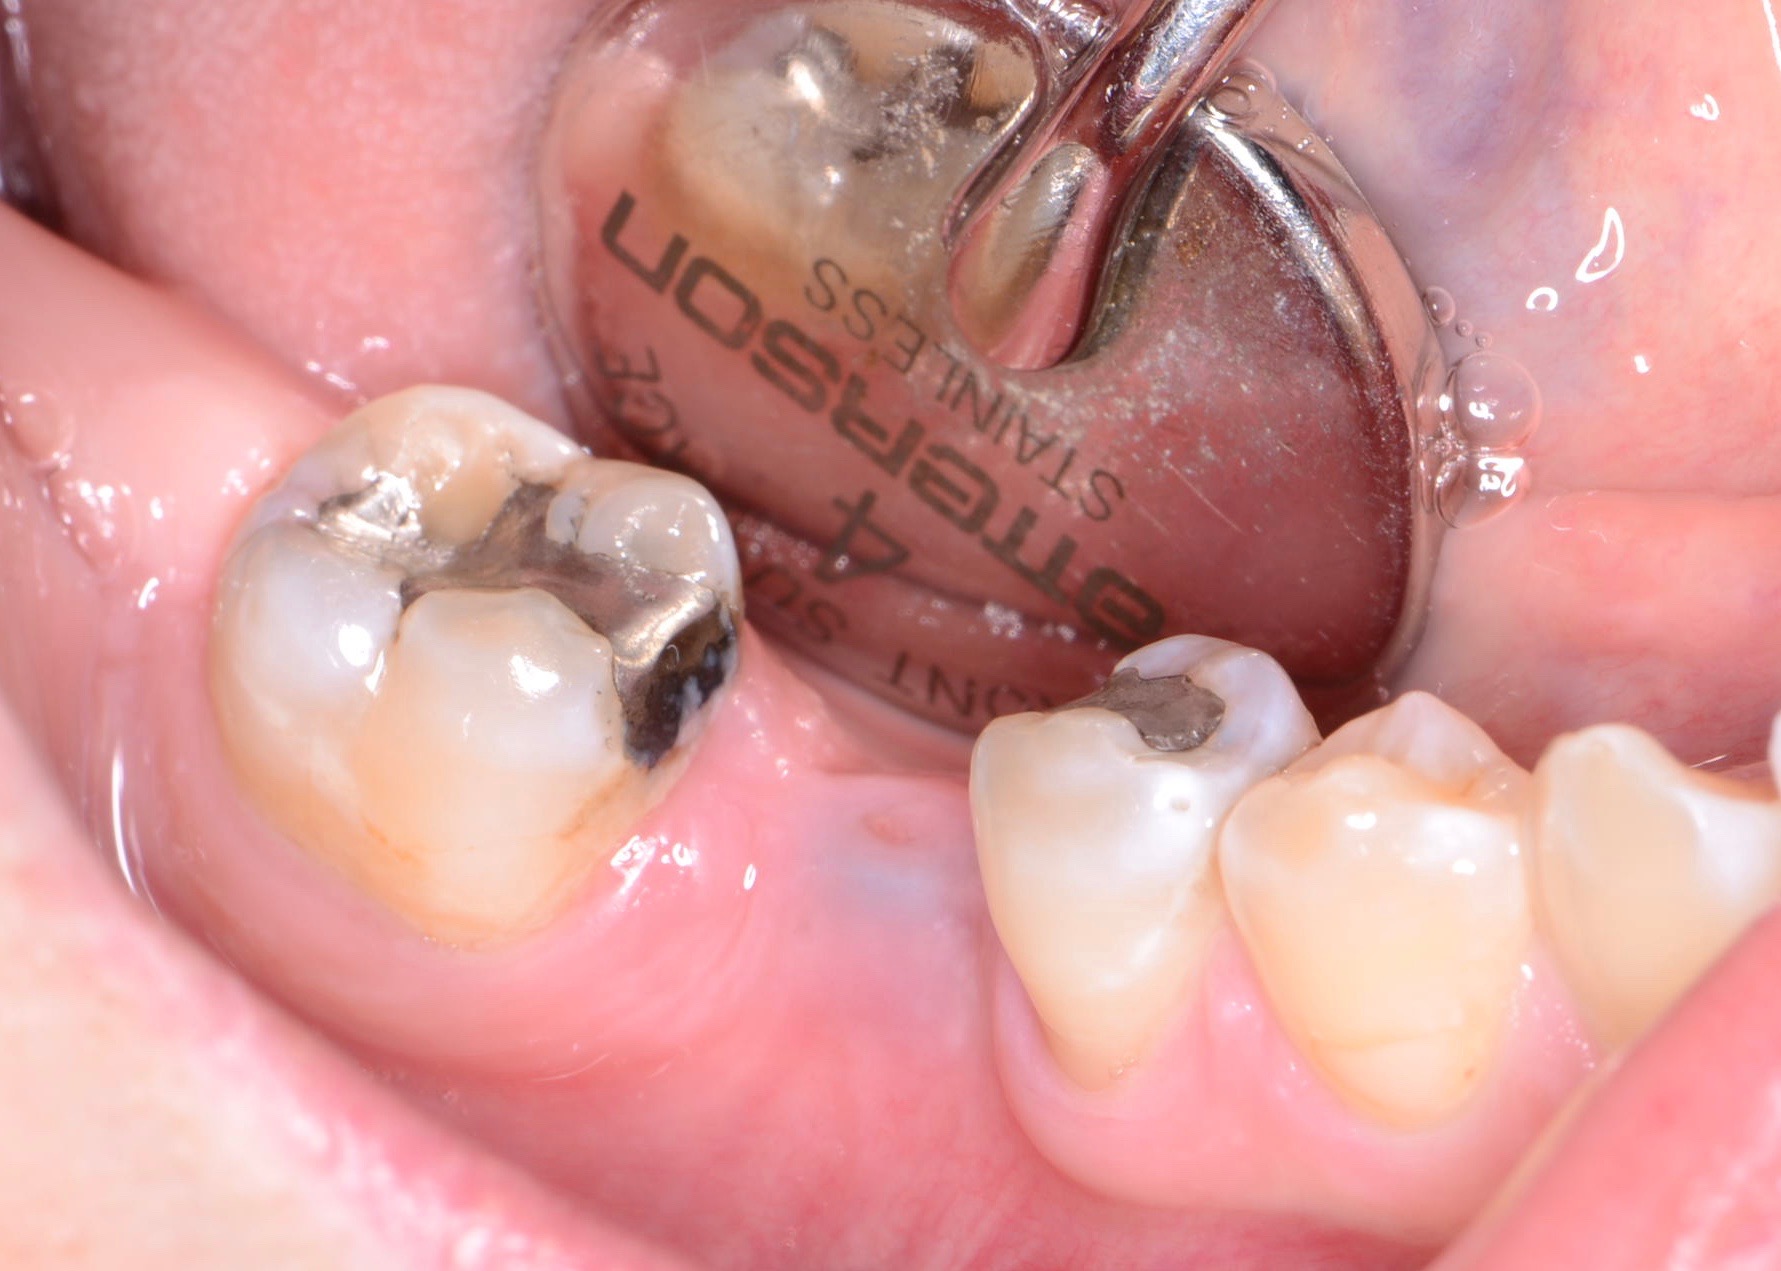

Fig 8. Loss of restoration and subsequent tissue overgrowth from broken abutment screw as shown in the radiograph (Fig 9).

Figure 8

Fig 9. Radiograph depicting fractured screw inside of the implant.

Figure 9